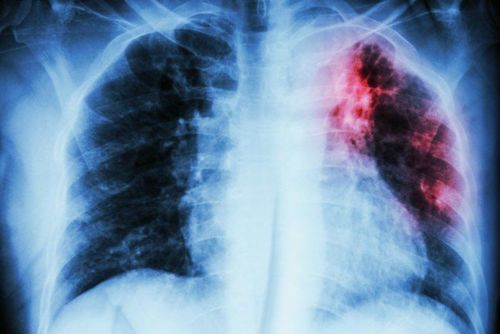

Chẩn đoán bệnh lao tiềm ẩn

Chẩn đoán bệnh lao tiềm ẩn là biện pháp giúp phát hiện sớm những người có nguy cơ mắc bệnh lao. Đặc biệt những người đã có thời gian tiếp xúc với người mắc lao phổi, để có biện pháp phòng ngừa và can thiệp hiệu quả.